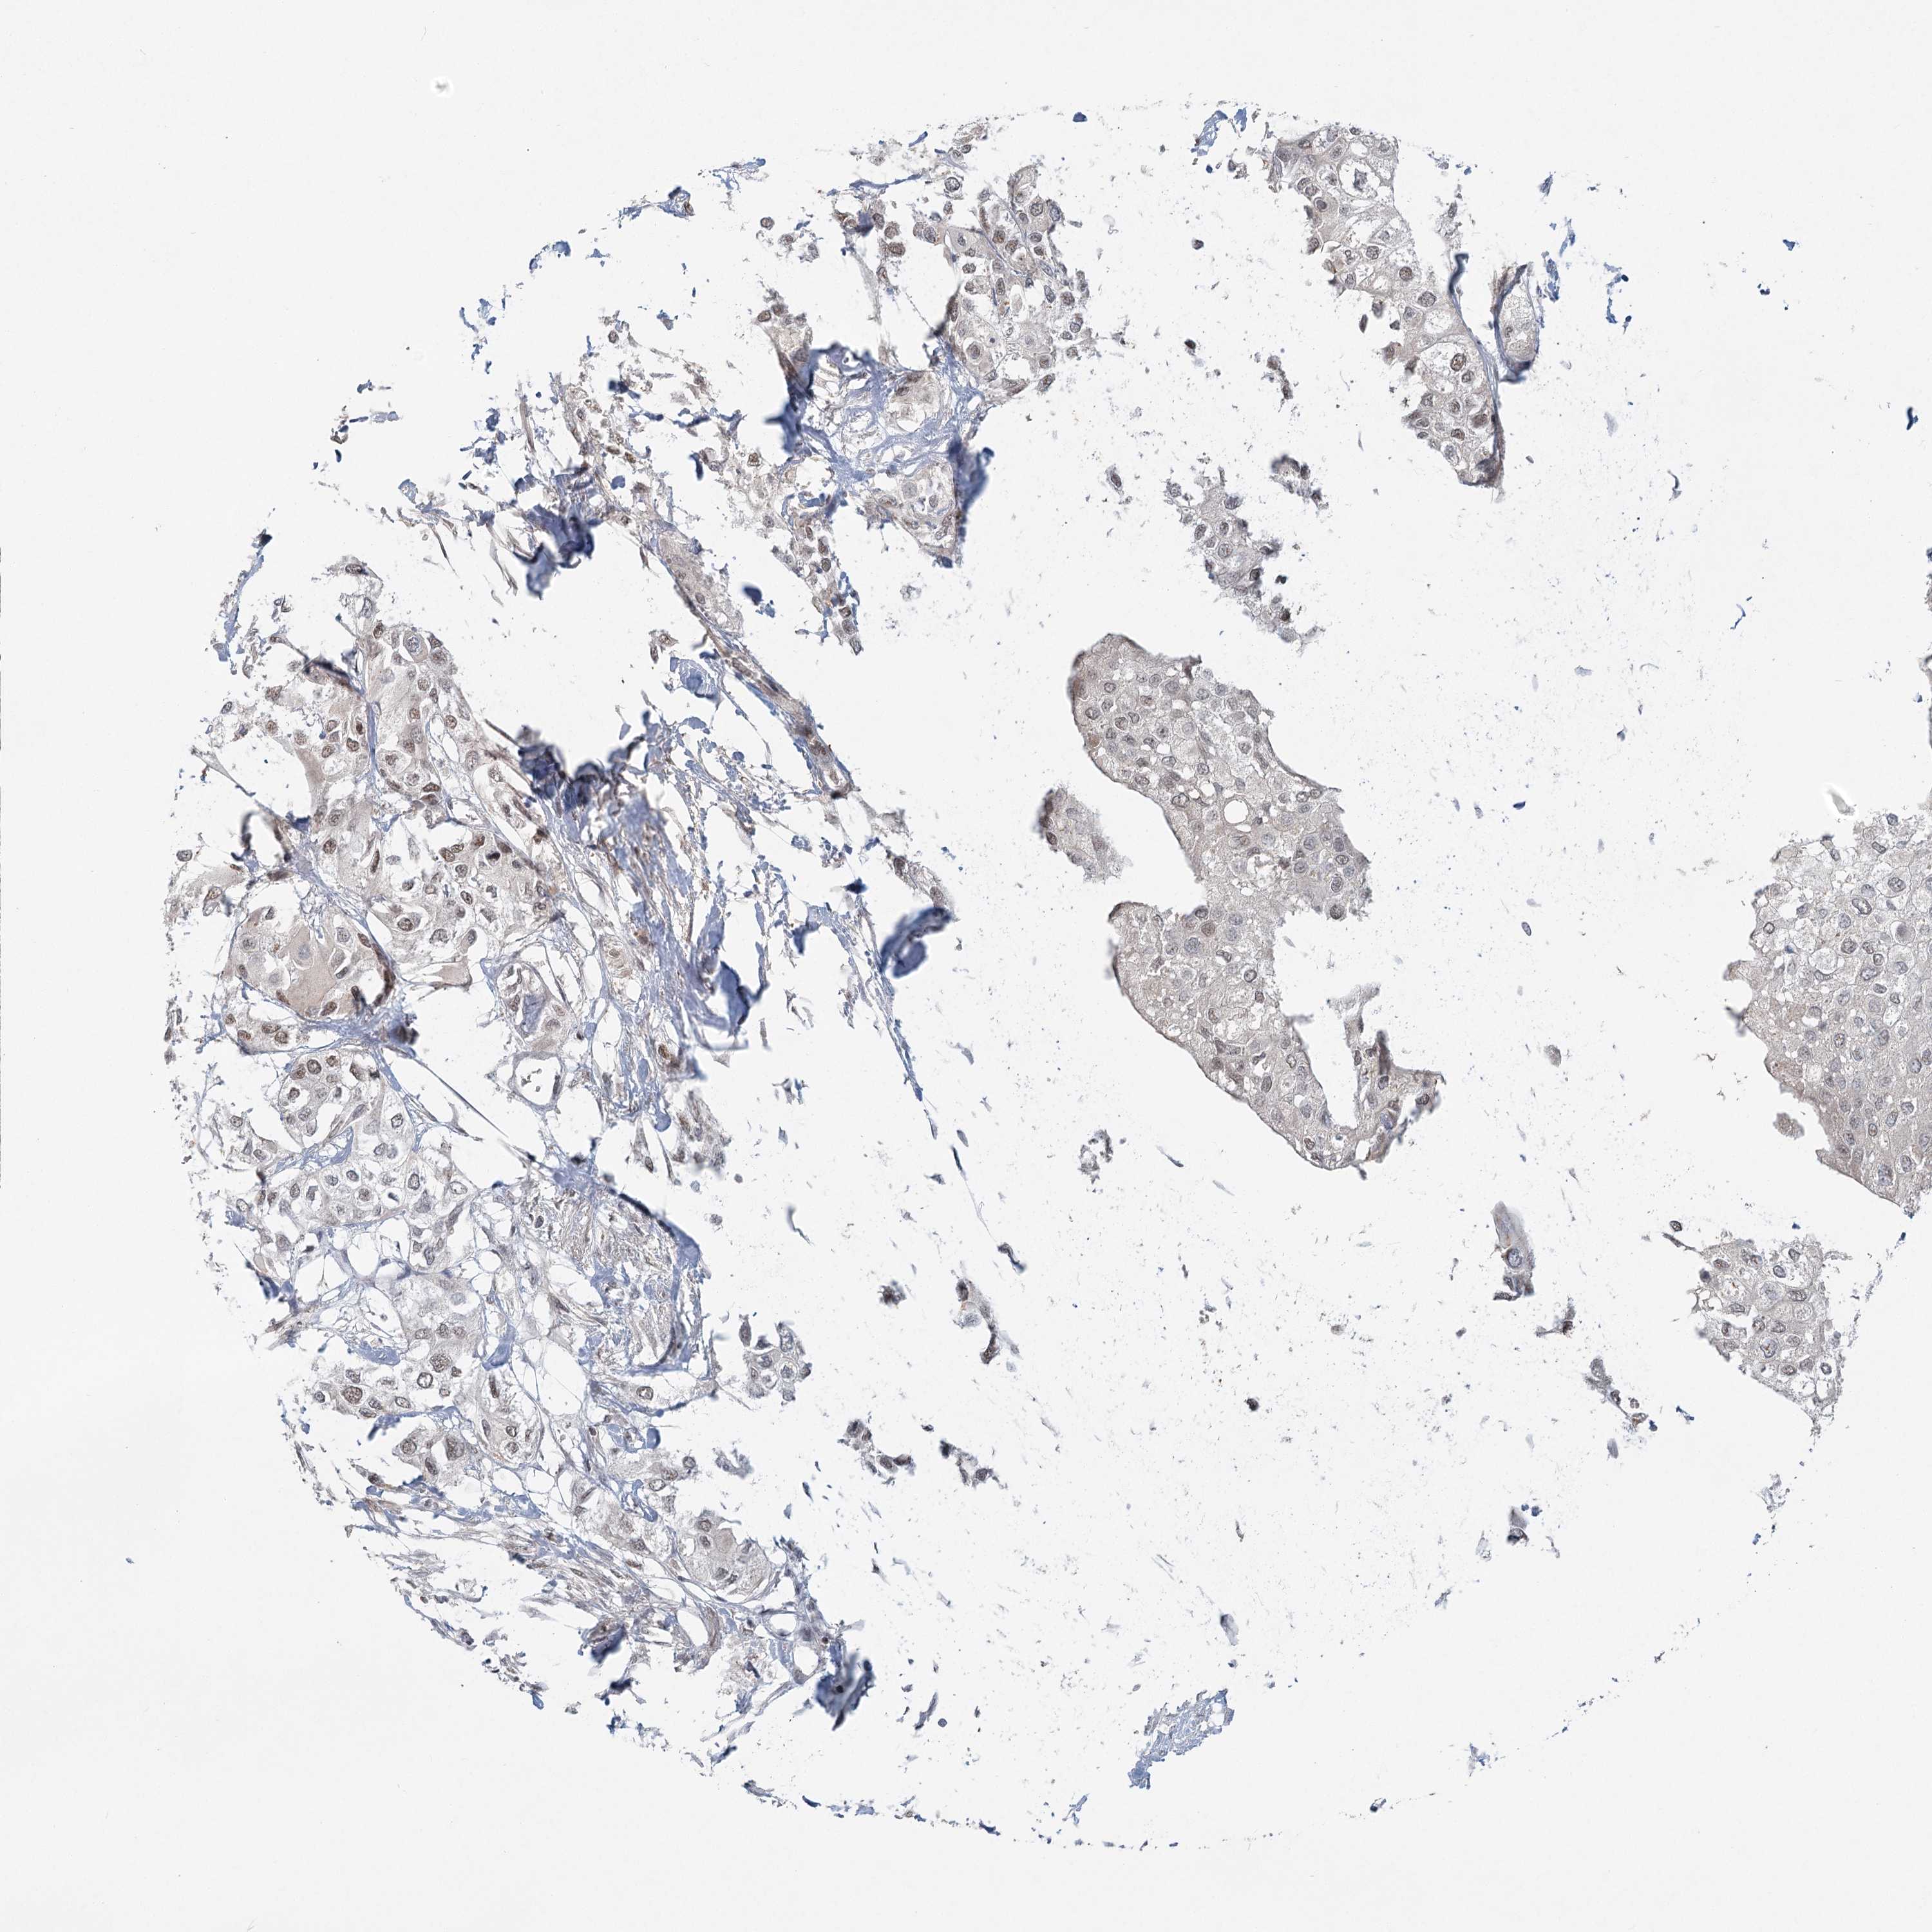

UROTHELIAL CANCER - Protein expressioni

A mouse-over function shows sample information and annotation data. Click on an image to view it in a full screen mode. Samples can be filtered based on level of antibody staining by selecting one or several of the following categories: high, medium, low and not detected. The assay and annotation is described here.

Note that samples used for immunohistochemistry by the Human Protein Atlas do not correspond to samples in the TCGA dataset.

Antibody stainingi

Antibody staining in the annotated cell types in the current human tissue is reported as not detected, low, medium, or high, based on conventional immunohistochemistry profiling in selected tissues. This score is based on the combination of the staining intensity and fraction of stained cells.

Each image is clickable and will lead to virtual microscopy that enables deeper exploration of all samples and also displays staining intensity scores, fraction scores and subcellular localization as well as patient and tissue information for each sample.

Antibody HPA037367

Staining

High

Medium

Low

Not detected

Intensity

Strong

Moderate

Weak

Negative

Quantity

>75%

75%-25%

<25%

None

Location

Nuclear

Cytoplasmic/membranous

Cytoplasmic/membranous,nuclear

Urothelial carcinoma, Low grade

Urothelial carcinoma, High grade